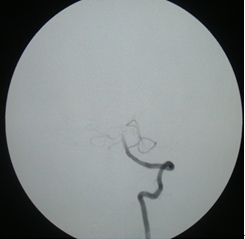

5:08进行基底动脉再通+支架取栓术。(图三)

图三:治疗后DSA示基底动脉再通